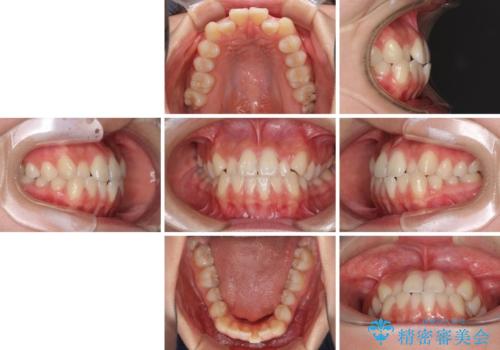

- 前歯のクロスバイトが気になり、インビザラインによる矯正治療を希望して来院された患者様です。

上顎側切歯(上の真ん中から2番目の歯)が舌側転位している場合、インビザラインでは仕上げきれないことが多く、更には無理して動かそうとすると歯髄壊死を起こすリスクが高いと言われています。

インビザラインで歯列を移動する前に、上顎前歯をワイヤー矯正で整え、その後上下歯列をインビザラインにて矯正治療を行うこととしました。

舌側転位している側切歯特有の、切縁の位置が不揃いであったり、根元が内側に引っ込んだ状態であったりという、インビザライン独特の仕上がりになることなく、きれいに整った歯列とすることができました。